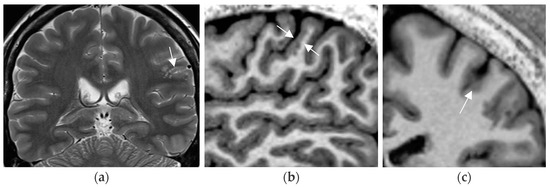

In a prior study [67] and in a recent prospective evaluation of the HARNESS protocol [68] in 123 and 131 patients, the sensitivity of MRI was particularly enhanced through interpretation by experienced readers for the diagnosis of hippocampal sclerosis and focal cortical dysplasia as the previously most frequently missed entities in adults and children, respectively. The combination of a dedicated MR and expert reader assessment increased detection of hippocampal sclerosis from 18 to 45% and of focal lesions from 50 to 91% [67]. Expert readers are more likely to recognize focal hippocampal sclerosis (Figure 2) and detect associated indirect signs such as atrophy of the ipsilateral fornix and mammillary body. Observations like the transmantle sign and subtle changes to adjacent white matter in focal cortical dysplasia and periventricular nodular and subcortical band heterotopia are challenging and less likely to be missed visually by an experienced reader.

Figure 2.

Hippocampal sclerosis depicted on coronal FLAIR (a) and T2 w sequence (white arrows) (b) (1.7 mm each) with volume reduction of the CA1-4 regions of the left hippocampus. FLAIR and T2 signal increases and slight atrophy of the left fornix (short arrow in (b)). Marked volume reduction of left temporal lobe as evidenced by the lower position of the left Silvian fissure (long arrow in (b)) compared to the right side.